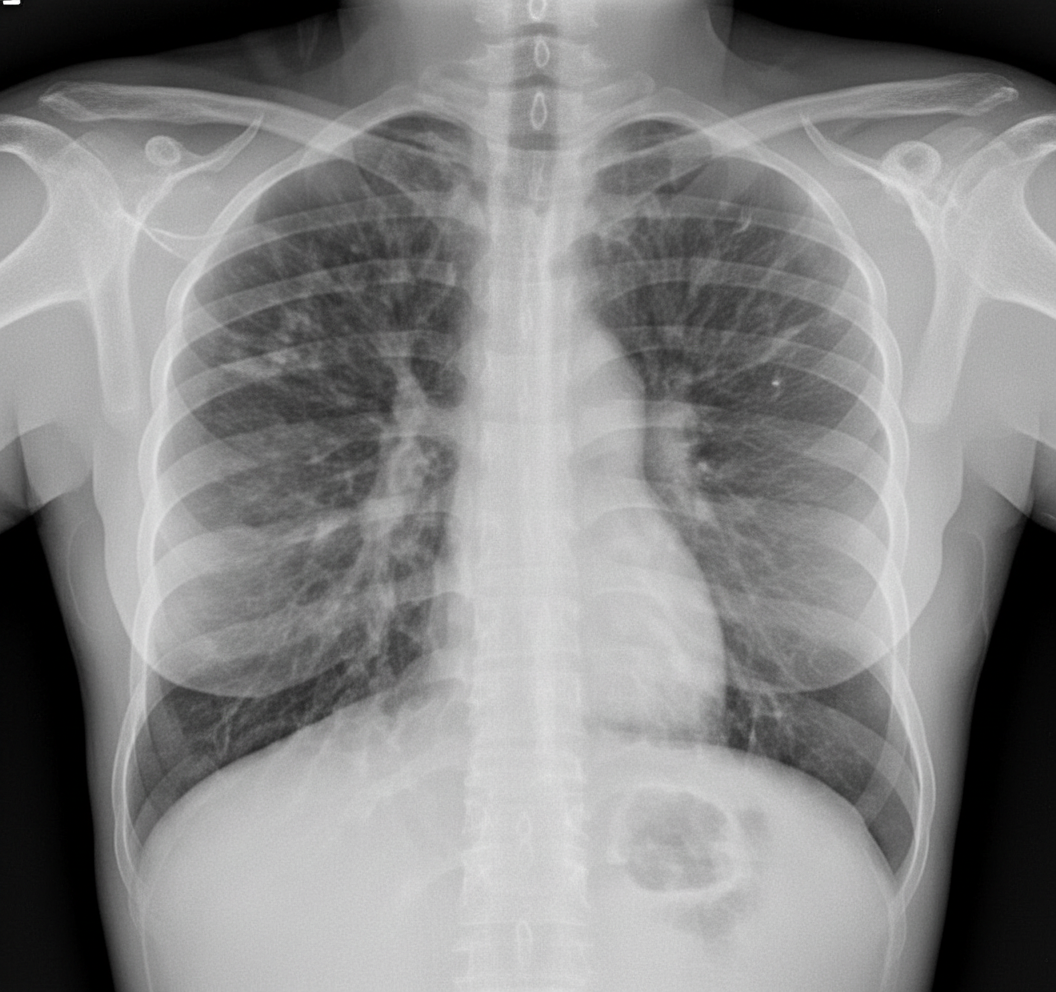

What does the CXR of a patient with cystic fibrosis show?

Explanation: ***Hyperinflation with bronchiectasis predominantly in upper lobes*** - Cystic fibrosis classically presents with **hyperinflation** (flattened diaphragm, increased anteroposterior diameter) due to chronic airway obstruction and air trapping - **Bronchiectasis with upper lobe predominance** is the hallmark feature, appearing as tramline shadows (dilated bronchi seen longitudinally) or ring shadows (dilated bronchi seen end-on) - Additional features include **peribronchial thickening**, **mucoid impaction**, and **cystic changes** in advanced disease - The upper lobe distribution distinguishes CF from other bronchiectasis causes *Bilateral pleural effusions with cardiomegaly* - This pattern suggests **congestive heart failure** or cardiac pathology - Not characteristic of cystic fibrosis, which primarily affects airways rather than cardiac structures *Bat wing pattern with Kerley B lines* - This describes **pulmonary edema** (cardiogenic or non-cardiogenic) - Kerley B lines represent interstitial edema, not seen in CF *Honeycombing in lower lobes with reticular opacities* - This pattern is typical of **usual interstitial pneumonia (UIP)** or **idiopathic pulmonary fibrosis** - CF affects upper lobes predominantly, not lower lobes, and causes bronchiectasis rather than fibrotic changes